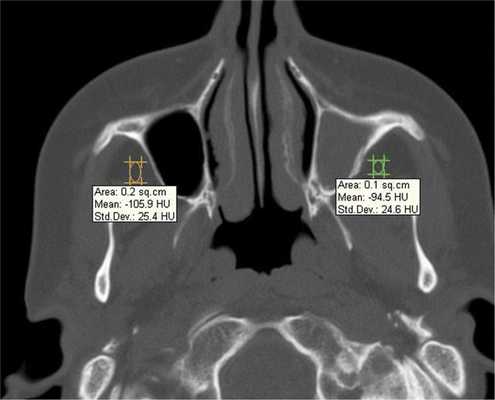

При воспалительных изменениях в ретроантральной жировой клетчатке верхнечелюстной пазухи на РКТ повышаются денситометрические значения ее плотности [10]. При одностороннем процессе отмечается выраженная асимметричность значений плотностей (рис. 4).

Рис. 4. Рентгеновская компьютерная томограмма околоносовых пазух. Аксиальная проекция, костное окно.

В 63,2% случаев на РКТ при выявлении одонтогенного верхнечелюстного синусита отмечалось уплотнение жировой клетчатки. Исследователи связывают это с переходом воспалительной инфильтрации пристеночной слизистой по периваскулярным пространствам к ретромаксиллярной клетчатке [7, 11, 12].